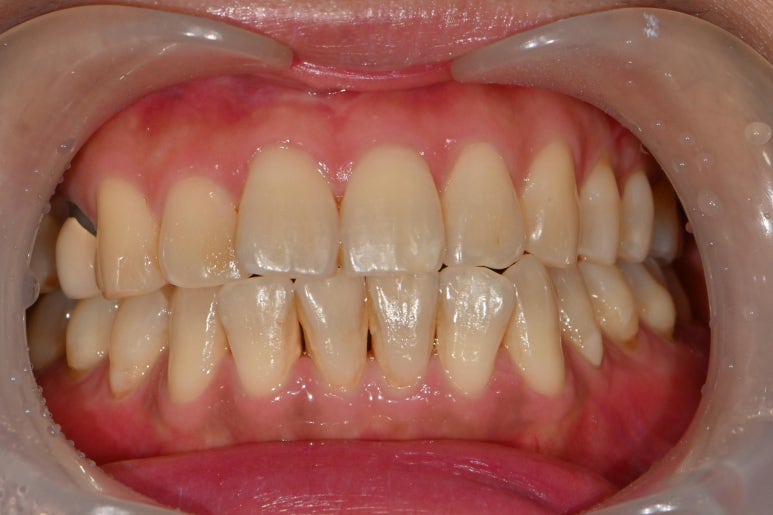

다 굳은 후 과잉의 본드필을

물이 나오는 기구를 이용하여 제거해주고

실을 제거해주면 위의 사진처럼 마무리가 됩니다.

본드필은 레진이나 gi와는 조금 다르게

양치질을 할수록 연마되어서 치아에

더 어울리는 색상과 형태가 나타납니다.

그래서 진료실에서는 과도한 연마를 하지 않습니다.